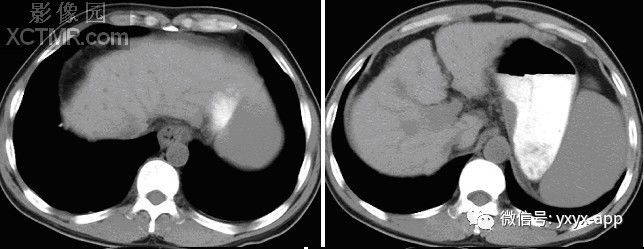

CT平扫

【影像表现】X线吞钡:食管下段迂曲,管壁呈锯齿状改变,粘膜皱襞增宽、增粗,扭曲呈蚯蚓状,并可见串珠状充盈缺损,食管稍扩张,管壁轮廓凹凸不平,钡剂排空延迟。管壁柔软,舒缩功能良好。 CT平扫及增强扫描可见食管内多发类圆形稍低密度病灶,动脉期未见明显强化,门脉期强化明显,与同层面主动脉强化程度相仿,显示病灶为血管性病变。肝脏大小比例失调,肝表面结节样不平,肝内密度尚均匀,未见明显局灶性密度异常及异常强化。

CT:增强三维重建可以明确曲张的范围及程度,尤其对食管旁静脉曲张及静脉曲张硬化治疗后随访有一定价值。影像表现为管壁增厚,管腔不规则,常合并胃底静脉曲张,除食管黏膜下或食管旁区外,肝胃韧带区可以出现卵圆形或葡萄状软组织影,增强扫描可以显示明显强化的迂曲血管团,呈持续强化,延迟性强化。